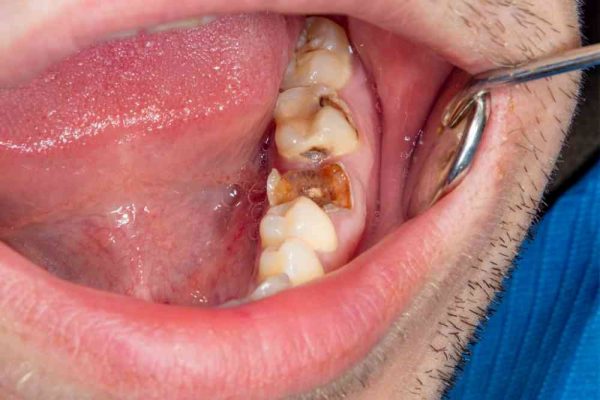

کدام دندان ها بیشتر مستعد پوسیده شدن و ایجاد حفره هستند؟

ایجاد حفره در دندان های مولر شایع تر از ایجاد حفره در دندان های جلوی شما است. احتمال ایجاد حفره در دندان های مولر، یا دندان های عقب دهان، بیشتر از ایجاد حفره روی روی دندان جلوی شما بیشتر است.

علت این است که دندان های عقب دهان دارای شیارها و فرو رفتگی های بیشتری هستند که می تواند باعث شود ذرات غذایی بیشتری در آنجا انباشته شوند.

علاوه بر این، احتمال داشتن حفره روی دندان های مولر نسبت به حفره دندان روی دندان های جلو شما بیشتر خواهد بود، زیرا تمیز کردن صحیح دندان های عقب خود می تواند دشوارتر باشد. با این حال، همه دندان های شما می توانند خراب شوند، بنابراین حتماً از همه آنها مراقبت کنید!

پوسیدگی و حفره دندان